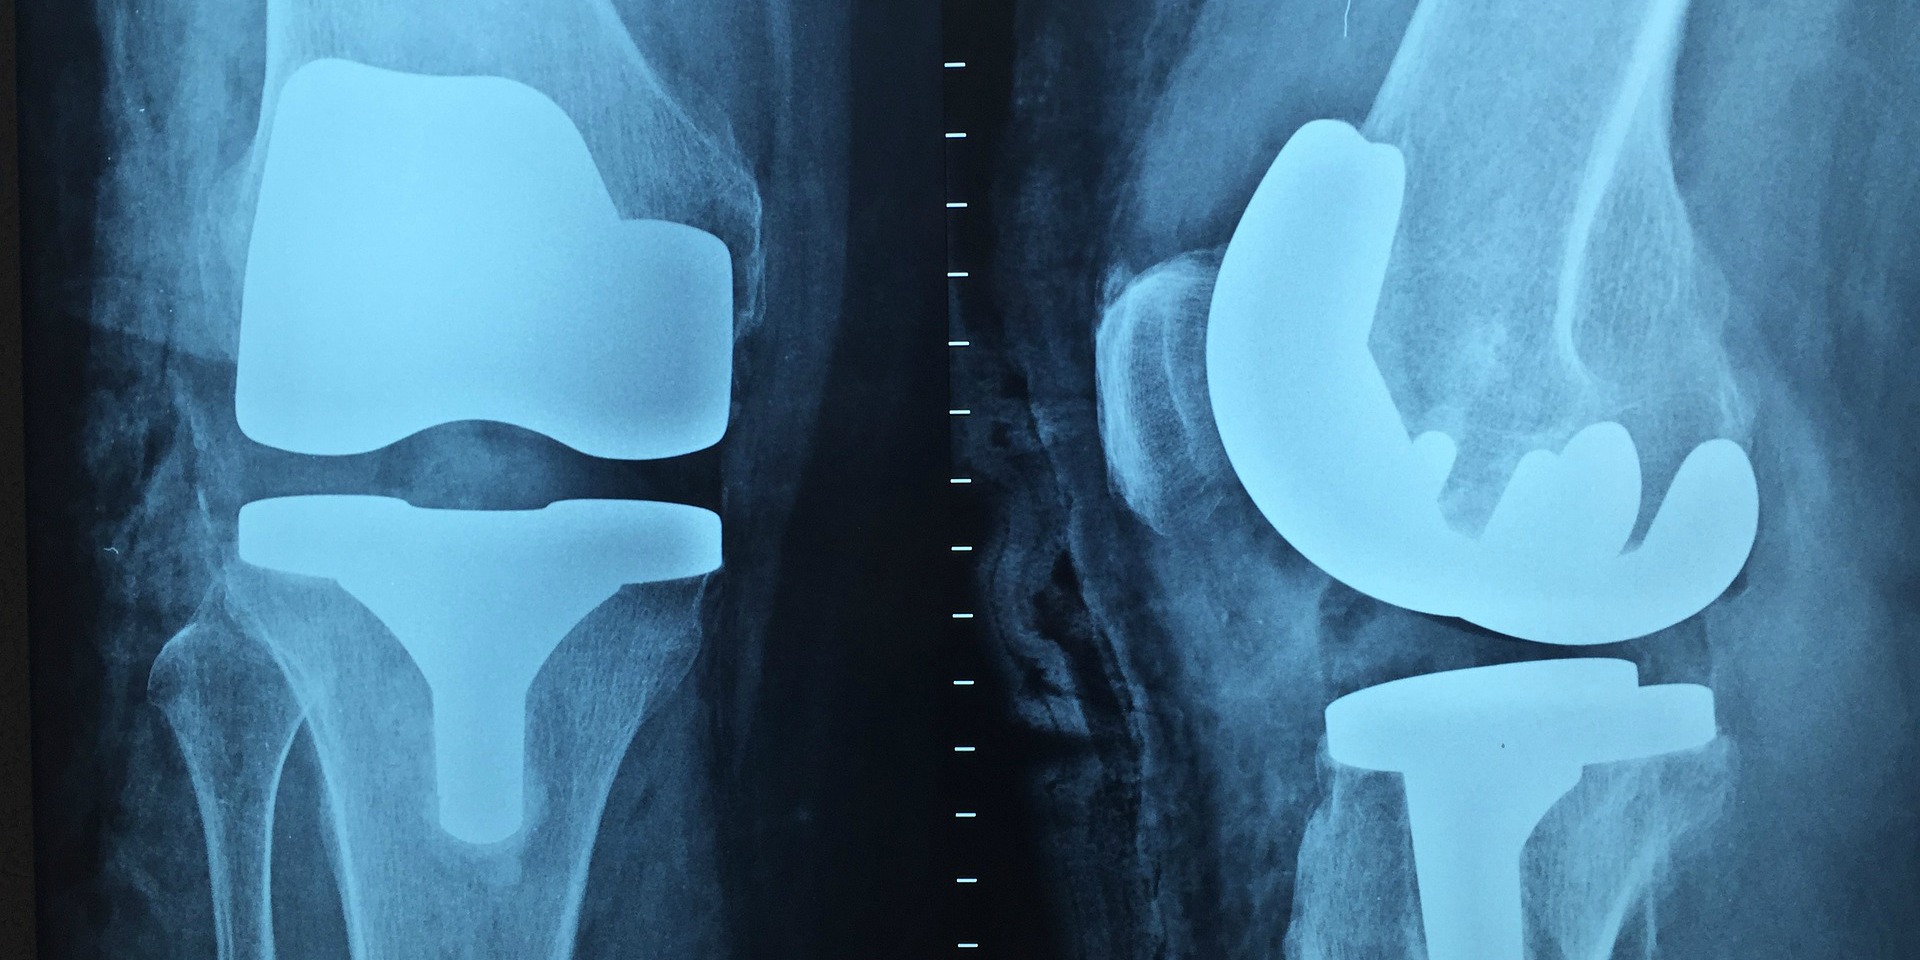

Die meisten Risse heilen nicht, weil es keine Blutzufuhr gibt und so die natürlichen Heilmechanismen nicht einsetzen können. Normalerweise behandelt man so eine Verletzung, indem man den verletzten Teil des Meniskus herausoperiert. Am Anfang funktioniert das noch sehr gut, aber auf lange Sicht funktionieren unsere Knie nicht ohne vollständigen Meniskus. Zum Beispiel kommt es zu Reibung der Knochenenden aneinander und das kann zu frühzeitiger Osteoarthritis führen. Sobald die Arthritis einsetzt, führt sie unaufhaltsam zu chronischem Schmerz und letztlich zu einem Gelenkersatz. Weil Meniskusrisse oft junge, sportliche Menschen betreffen, kann dies viele Jahre der Einschränkung durch Arthritis und einen großen Kostenaufwand für das Gesundheitssystem bedeuten.